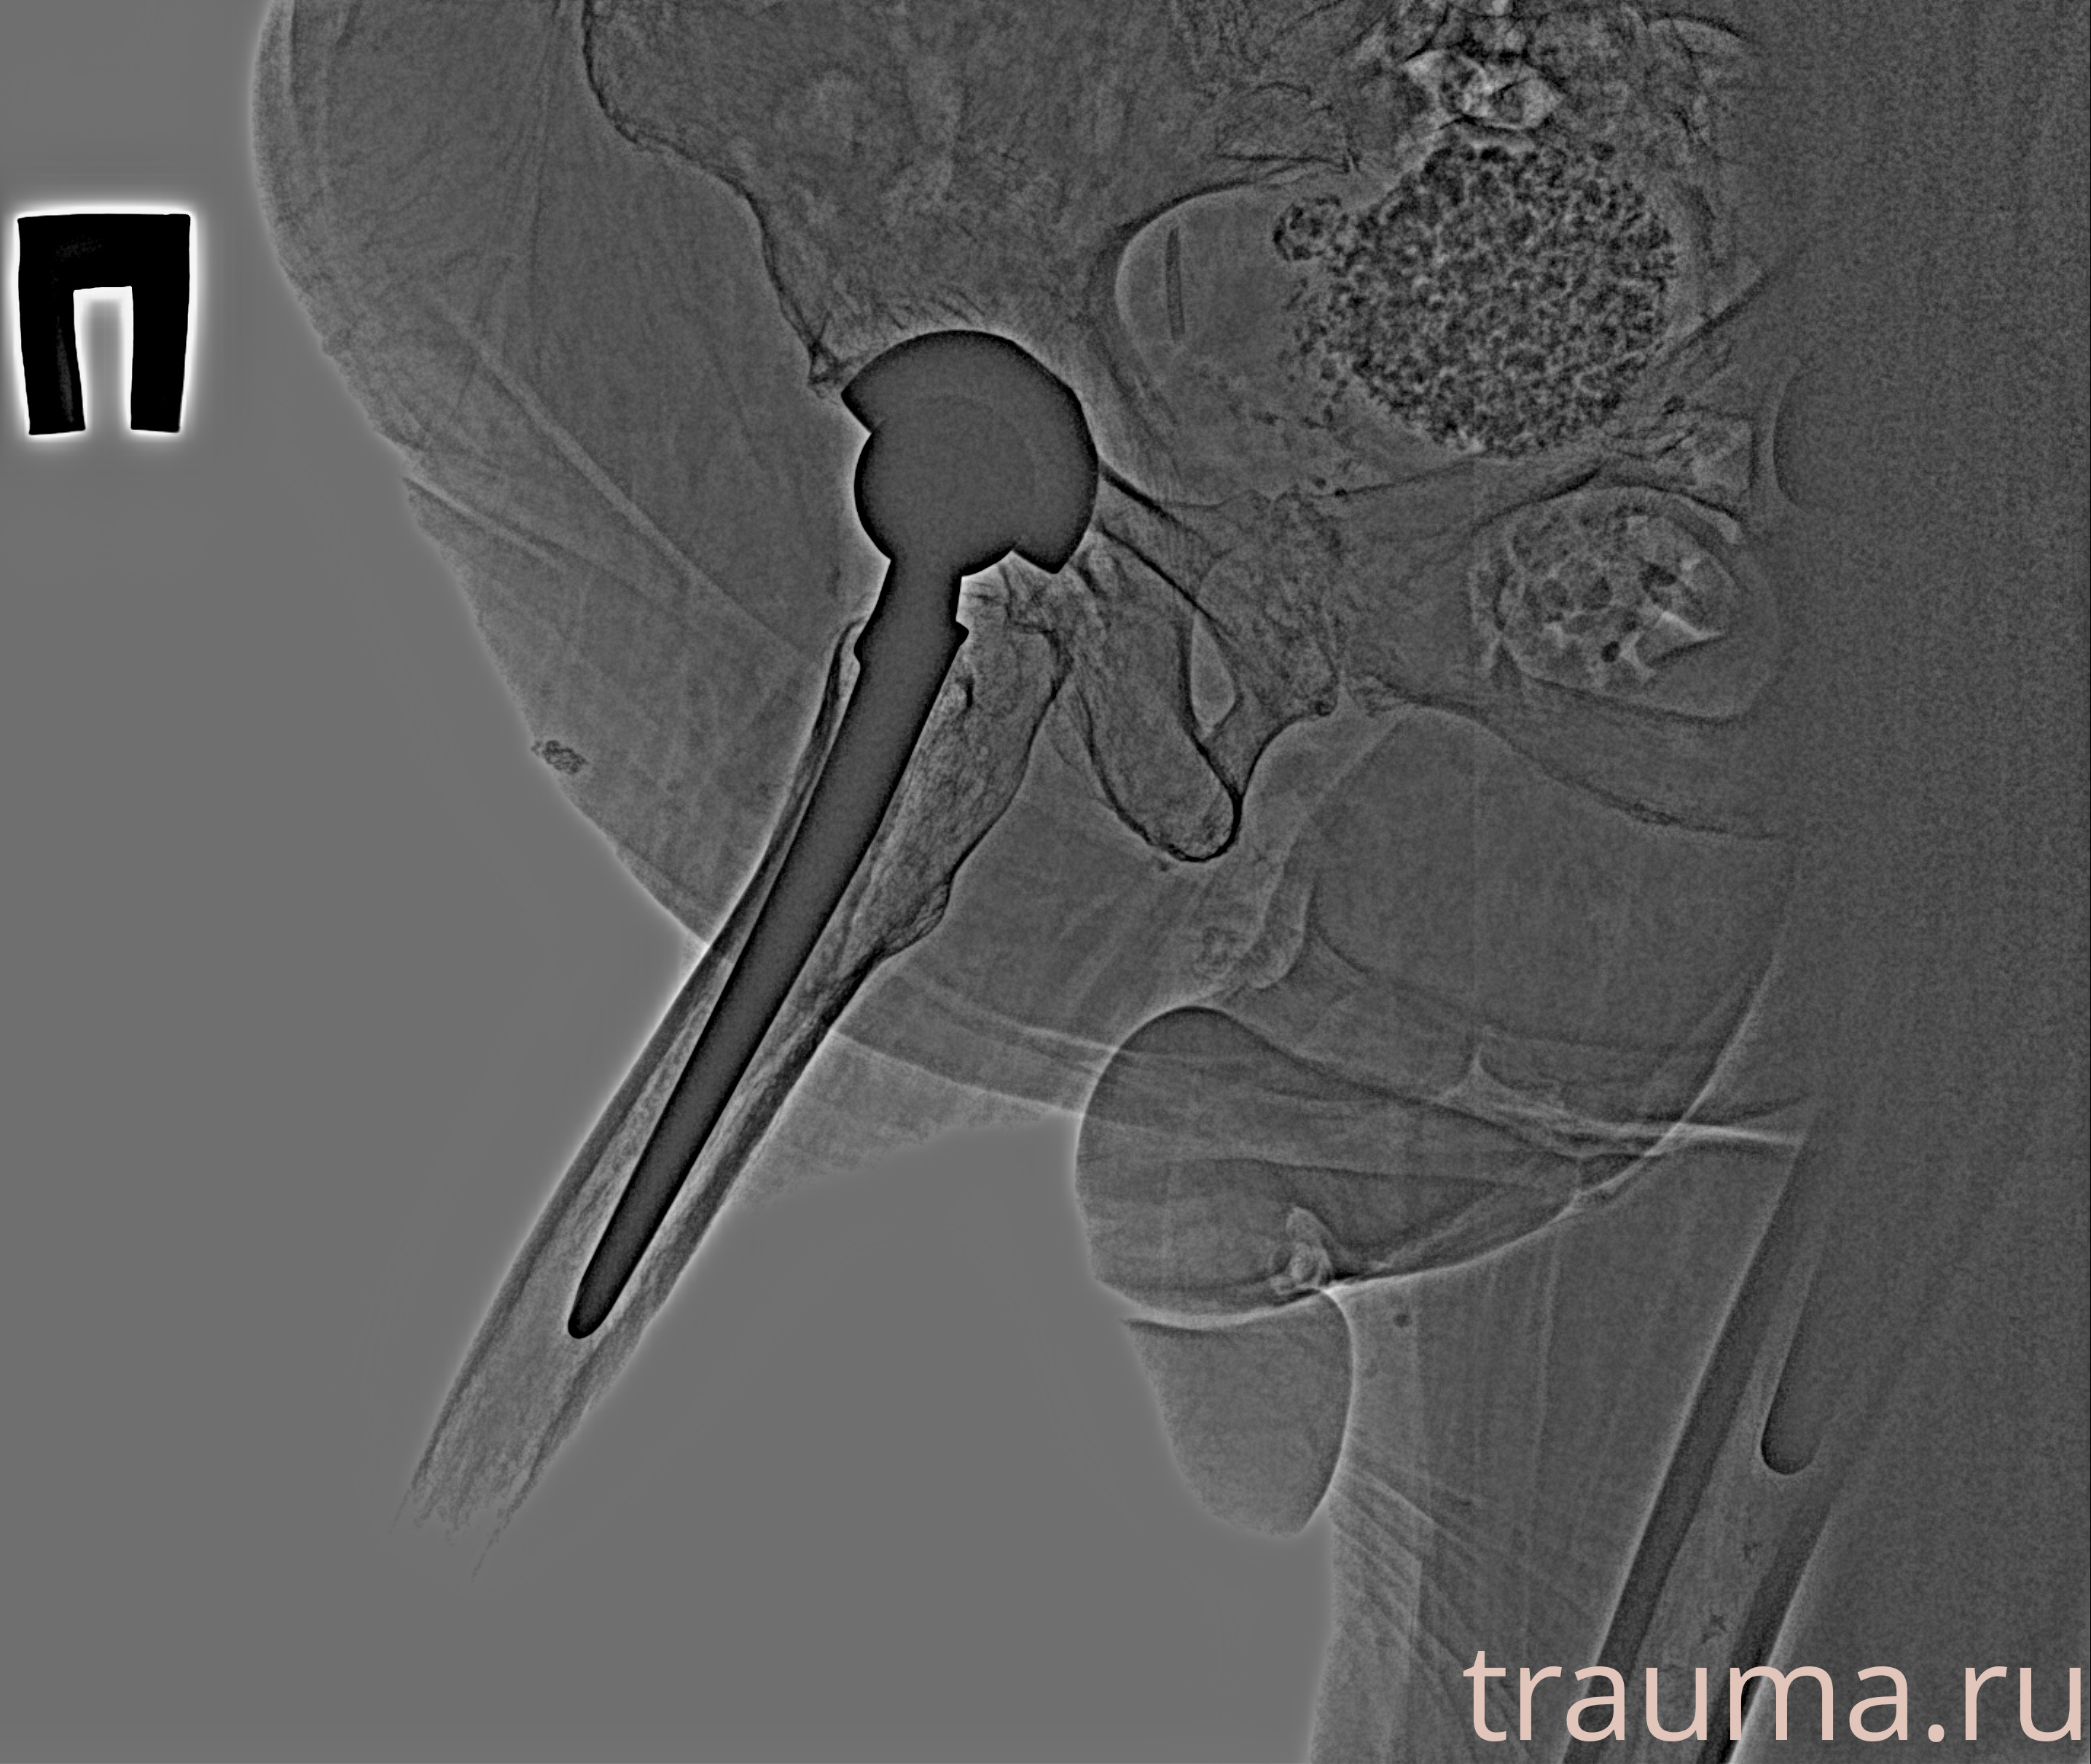

Рентгенограммы

Рентген на дому: по вашему адресу приезжает врач-рентгенолог, травматолог-ортопед с мобильным рентгеновским аппаратом, проводит диагностику травмы или заболевания, делает необходимые рентгенограммы, дает рекомендации по дальнейшему лечению. Получить качественные снимки в домашних условиях возможно благодаря уникальной методике, разработанной МосРентген Центром для института  Склифосовского

Яркость: 1   Контраст: 1   Инвертировать: 0 Увеличение: 1

Перетаскивайте мышь вверх/вниз для контраста, влево/право для яркости. Прокрутка колесом изменяет масштаб. Нажмите Сбросить для возврата к исходному изображению. При увеличении держите мышь в той области, которую хотите рассмотреть.